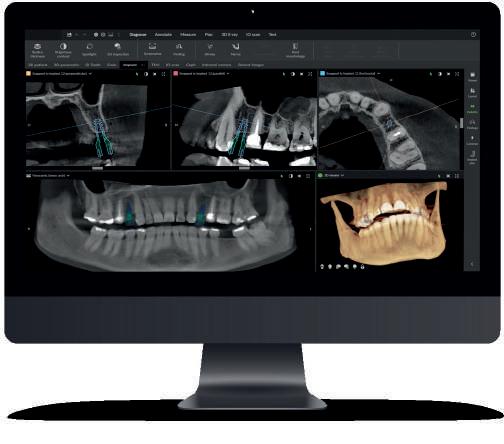

Utilizarea și maximizarea mijloacelor vizuale. Camerele intraorale, scanerele și fotografiile pre- și post-tratament sunt câteva exemple de mijloace vizuale care ajută la educarea, motivarea și activarea pacien-

ților pentru a accepta și a continua tratamentul.

Experiența pacientului. Pe lângă mijloacele vizuale și abilitățile de comunicare, există multe alte aspecte ale unui praxis stomatologic care pot ajuta la maximizarea experienței pacientului, cum ar fi: ușurința de a programa o ședință, modul în care pacientul este gestionat în fiecare tranziție a ședinței, condiția generală a facilității, brandul cabinetului, procesul de monitorizare a pacientului și ușurința cu care pacienții obțin ceea ce își doresc sau au nevoie. Când un cabinet pune accent pe îmbunătățirea continuă a experienței pacientului, de la tehnologie la facilități și până la serviciile oferite, crește nivelul de valoare perceput de pacienții existenți și de cei potențiali. Instruirea în abilitățile de comunicare ar trebui să fie o prioritate. Așa după cum afirma fondatoarea firmei autorului, Cathy Jameson, PhD: „nu există status quo; fie urci, fie cobori.” De aceea, fii pe o cale continuă de îmbunătățire.

managerul trebuie să fie familiarizat cu cele mai noi instrumente și tehnologii. Softurile de gestionare a pacienților sunt esențiale pentru o clinică modernă. Un DOM bine pregătit știe să folosească aceste tehnologii în favoarea clinicii, eficientizând operațiunile și reducând erorile administrative. Capacitatea de a adapta clinica la noile tendințe, inclusiv introducerea de soluții digitale care să îmbunătățească experiența pacientului, poate diferenția o clinică de succes de una care stagnează sau irosește resurse financiare, umane și de timp prin procese învechite.